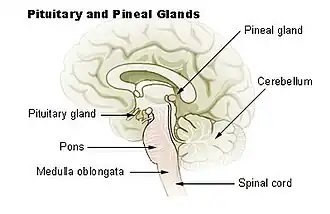

Hipófise e pineal

Hipófise e pineal Sistema endócrino